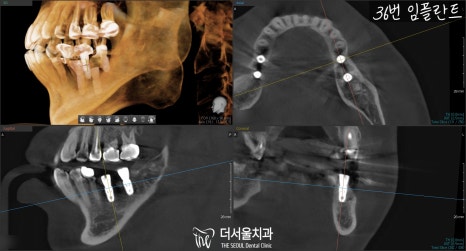

픽스처 식립 후 3D CT로

잘못 심어진 것은 없는지,

올바른 위치에 계획했던 대로

잘 심어졌는지 확인합니다.

별다른 문제없이 잘 심어졌군요. ^^

『결과』

빈 자리었던 곳까지

총 4개 임플란트 수술은

잘 끝마치게 되었습니다.